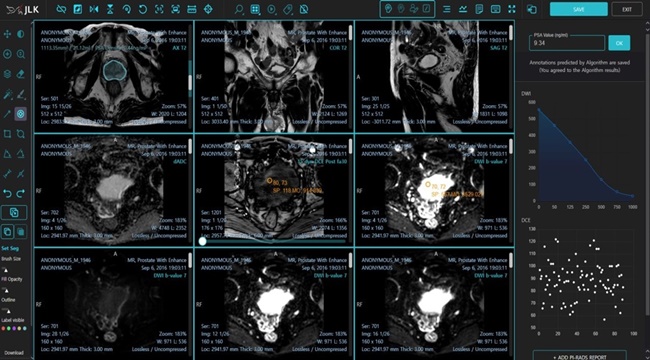

전립선암의 진단과 추적에는 다중 매개변수(Multiparametric) 전립선 MR 영상이 활용되며, 질병에 대한 조직학적 이해 및 MR 영상에 대한 많은 경험이 필요하다.

또한 판독의사들의 숙련도에 따라 진단의 난이도가 있는 질환으로 세계적으로 인증된 바이오 마커인 PIRADS(Prostate Imaging Reporting and Data System) 점수를 표준화해 사용하고 있다.

MEDIHUB Prostate는 인공지능을 활용해 다중 매개변수 전립선 MR 영상을 복합적으로 분석하고 AI가 PIRADS 진단 및 PSA(전립선 특이 항원, Prostate-Specific Antigen) density 진단 등의 전립선암 진단에 필요한 모든 데이터를 제공한다.